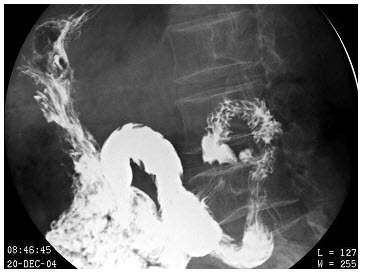

171、单项选择题

男,2岁,阵发性哭闹不安1天,频繁呕吐,腹部拒按,腹部触诊脐右上方可触及包块,行钡灌肠检查,如图所示,最可能的诊断为()

A.肠扭转

B.结肠癌

C.肠穿孔

D.肠套叠

E.以上都不是